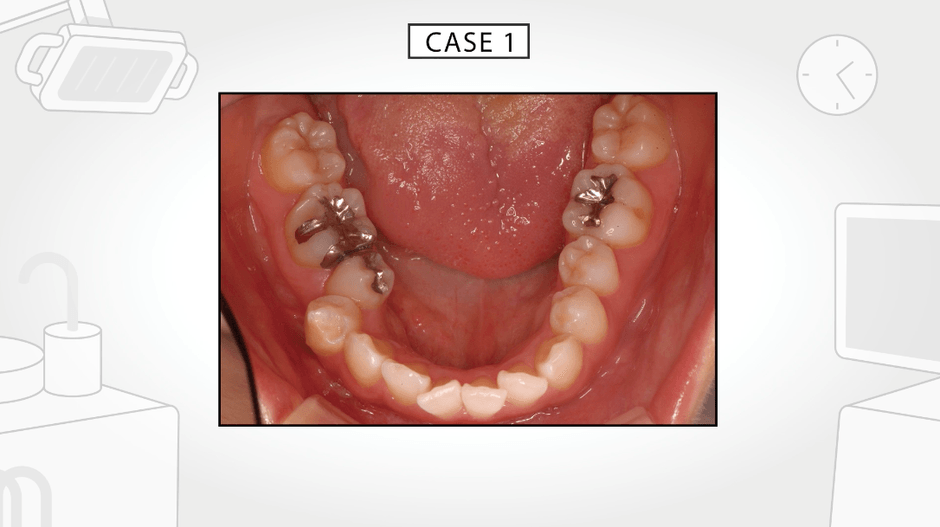

今回発表した動画は、それらの不定愁訴を引き起こしている原因が口内の舌の緊張によるものであることを示し、さらに、その要因は現代人の食生活が引き起こした顎や歯に見られる身体的特徴ということを解説しています。